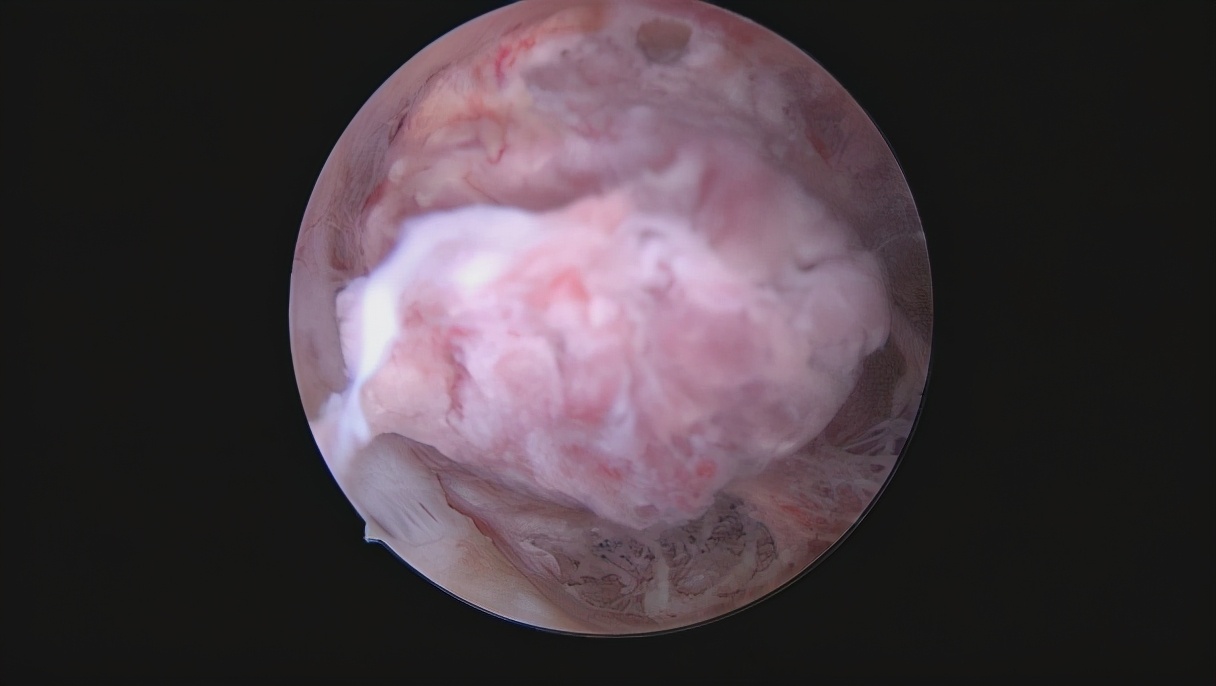

子宫内膜癌宫腔图片

注:月经异常的广大 妇女及时 就诊!!!